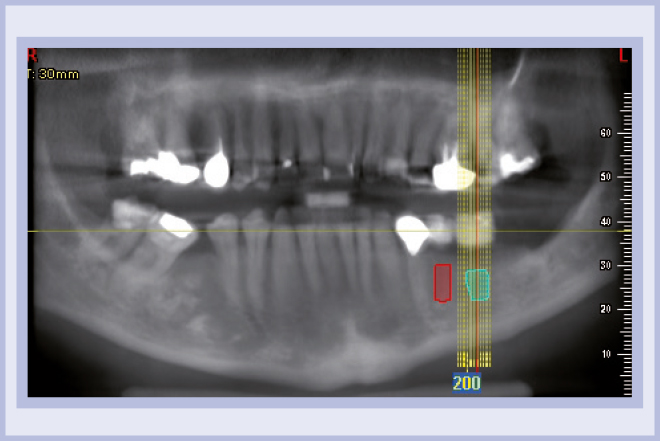

Per riabilitare la masticazione del terzo quadrante, con osso gravemente atrofico, si procede allo studio del caso con esame radiologico 3D e posizionamento virtuale di impianti Exacone® Leone. La prima valutazione è stata eseguita con il software dell’apparecchio radiografico Cone Beam presente in studio. Dopo aver verificato che la quantità di osso residuo fosse sufficiente all’inserimento di due impianti, seppur di dimensioni ridotte, in sede 3.5 e 3.6 senza l’ausilio di tecniche di rigenerazione ossea (Figg. 1-3), si richiede al laboratorio di confezionare una mascherina radiologica con ceratura diagnostica radiopaca e repere standardizzato a livello incisale come da protocollo Leone (Figg. 4, 5). Si verifica quindi clinicamente l’assenza di mobilità della mascherina dopo il posizionamento nel cavo orale del paziente (Figg. 6, 7). Si effettua una CBCT con la mascherina in posizione e l’esame viene inviato in formato DICOM all’azienda Leone assieme al modello master della paziente. L’azienda provvede quindi ad inviare agli Autori il software 3Diagnosys (software di progettazione) in licenza monopaziente con caricati i file DICOM ricevuti; il software viene quindi utilizzato per la progettazione definitiva del caso (Figg. 8-12).

- Figg. 8-12 – Pianificazione implantare con software 3Diagnosys Leone

- Fig. 9

- Fig. 10

- Fig. 11

- Fig. 12